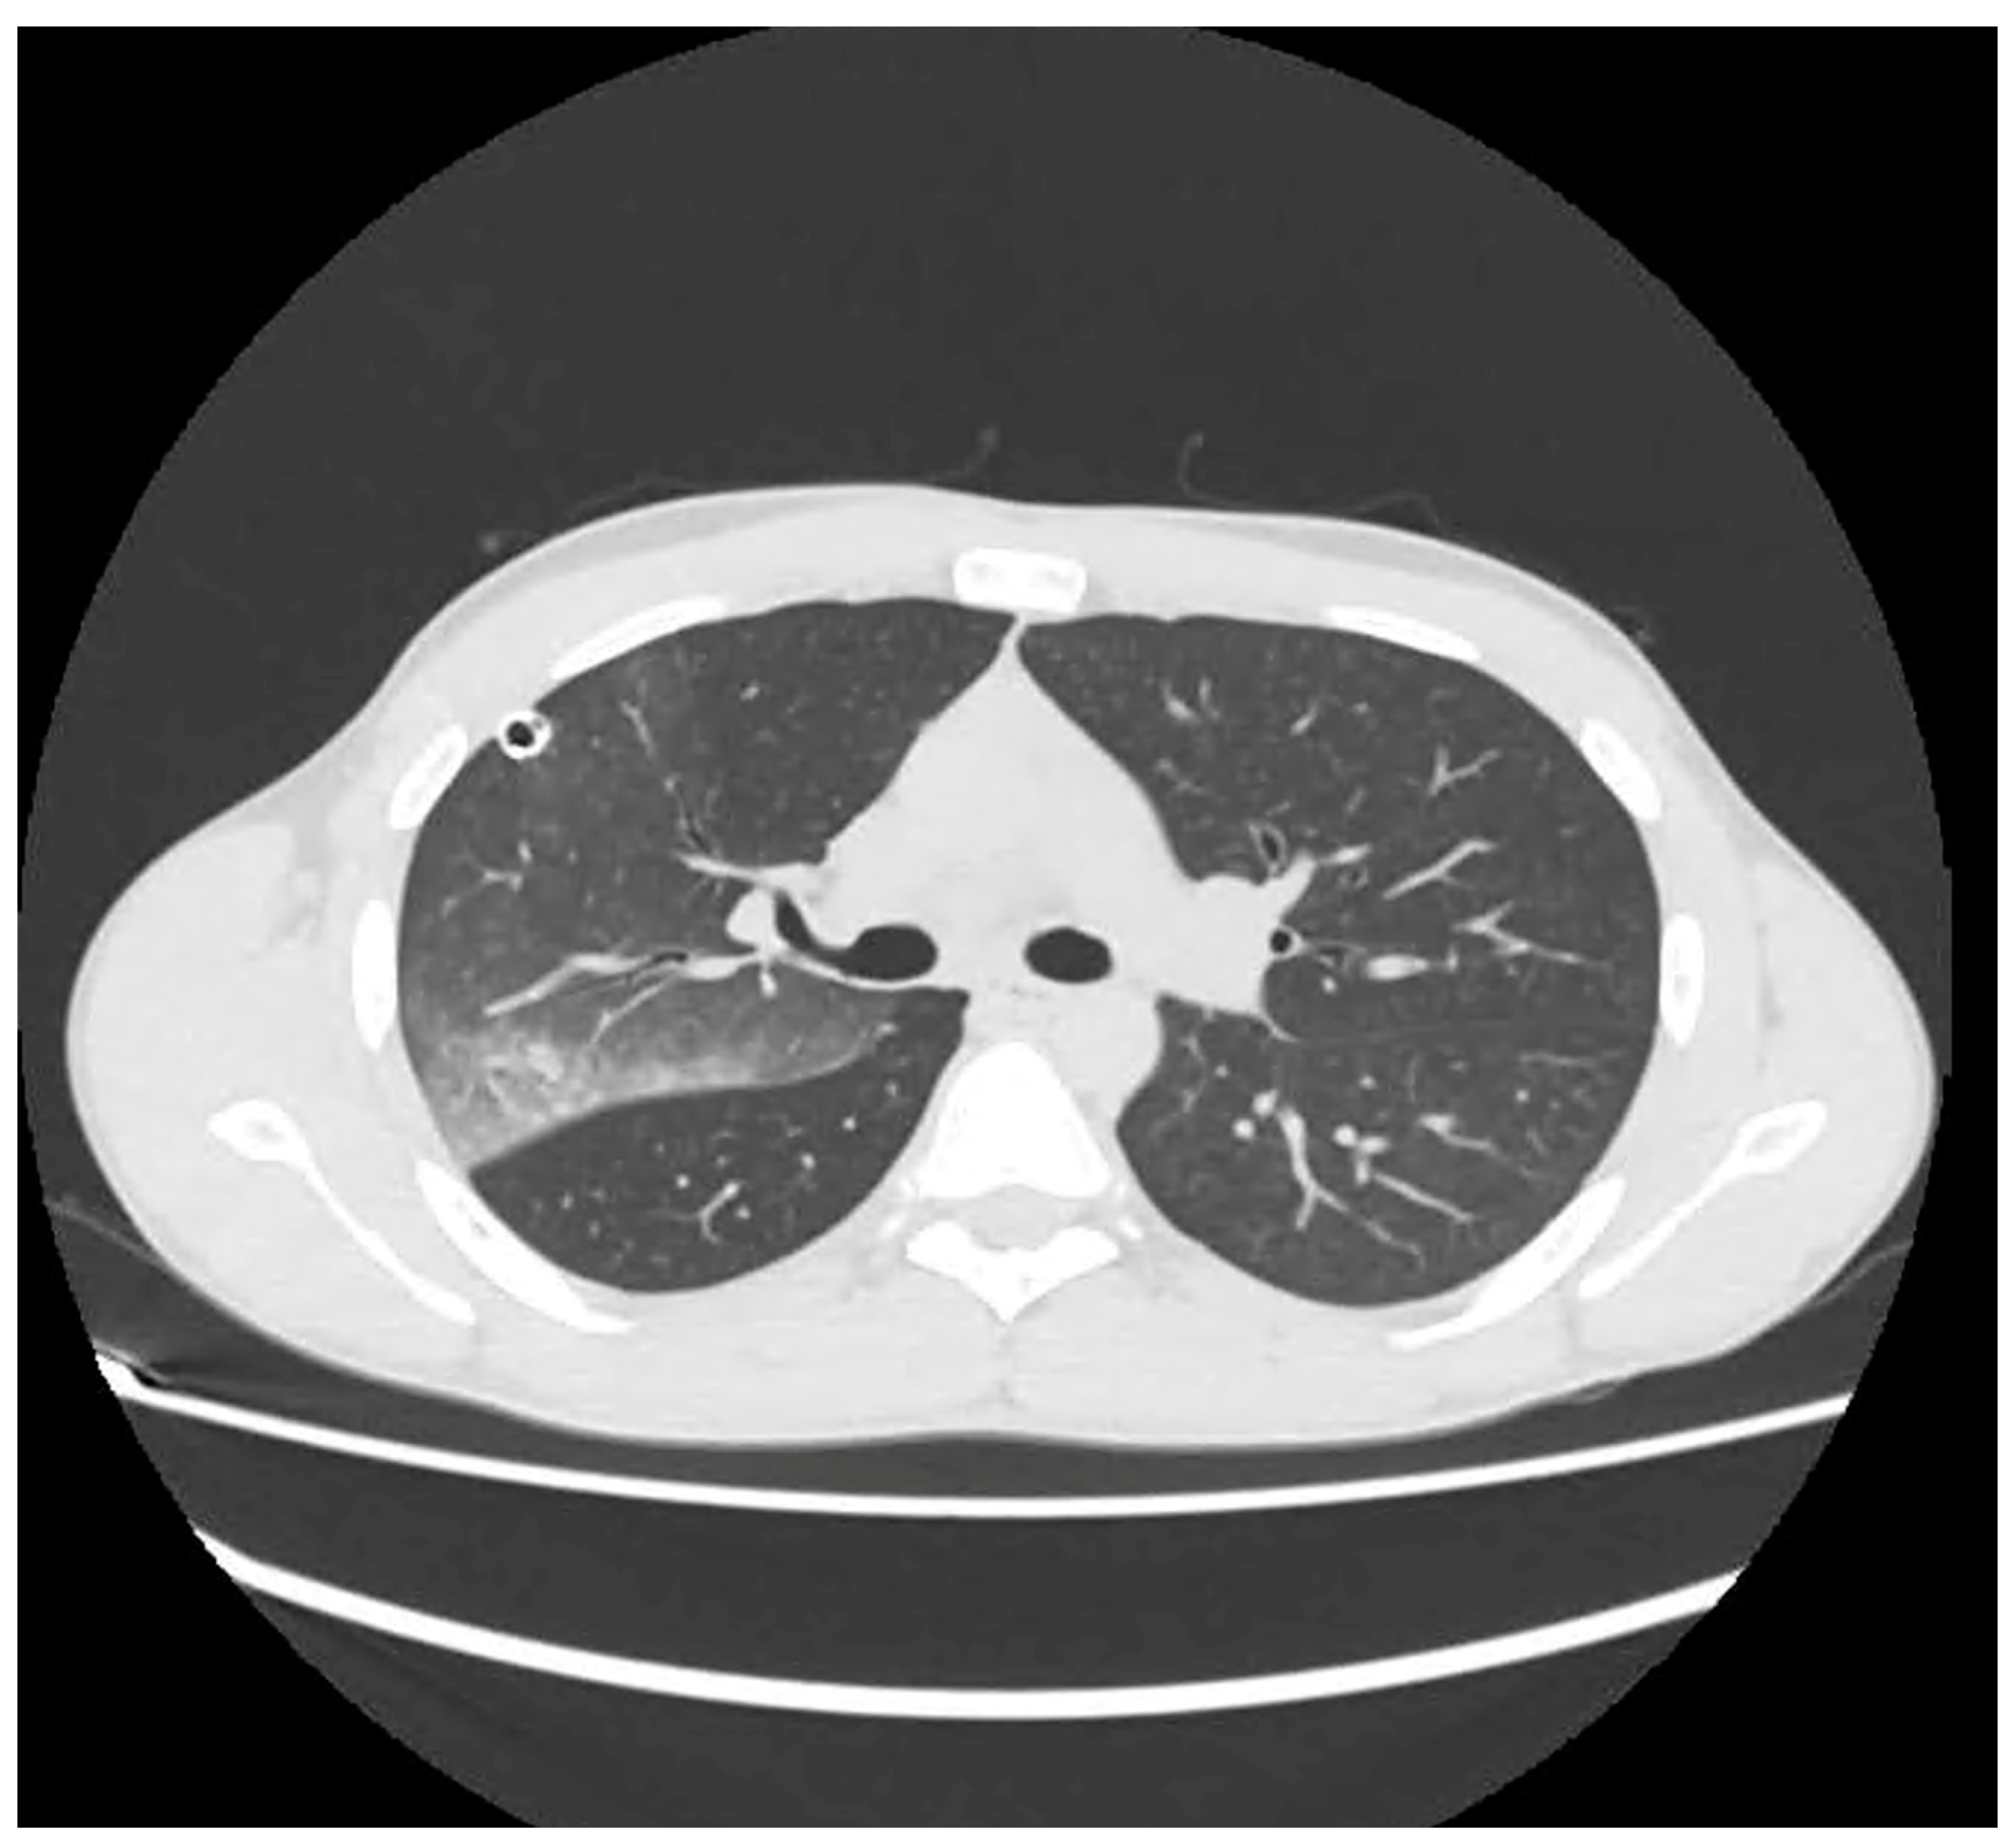

3.1. Case 1